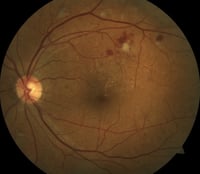

► Traditional fundus photography, while essential for documenting retinal findings from a comprehensive exam, can only capture images of the posterior pole, i.e., about 45 degrees of the back of the eye. Widefield retinal imaging, however, uses scanning lasers to produce images representing up to 200 degrees. Therefore, it enables detection of pathology in the peripheral retina that would not be detected with traditional retinal photography or slit lamp exam. A growing body of research shows that many retinal disease processes manifest first in the periphery.

![]() |

| Fundus photography of proliferative diabetic retinopathy |